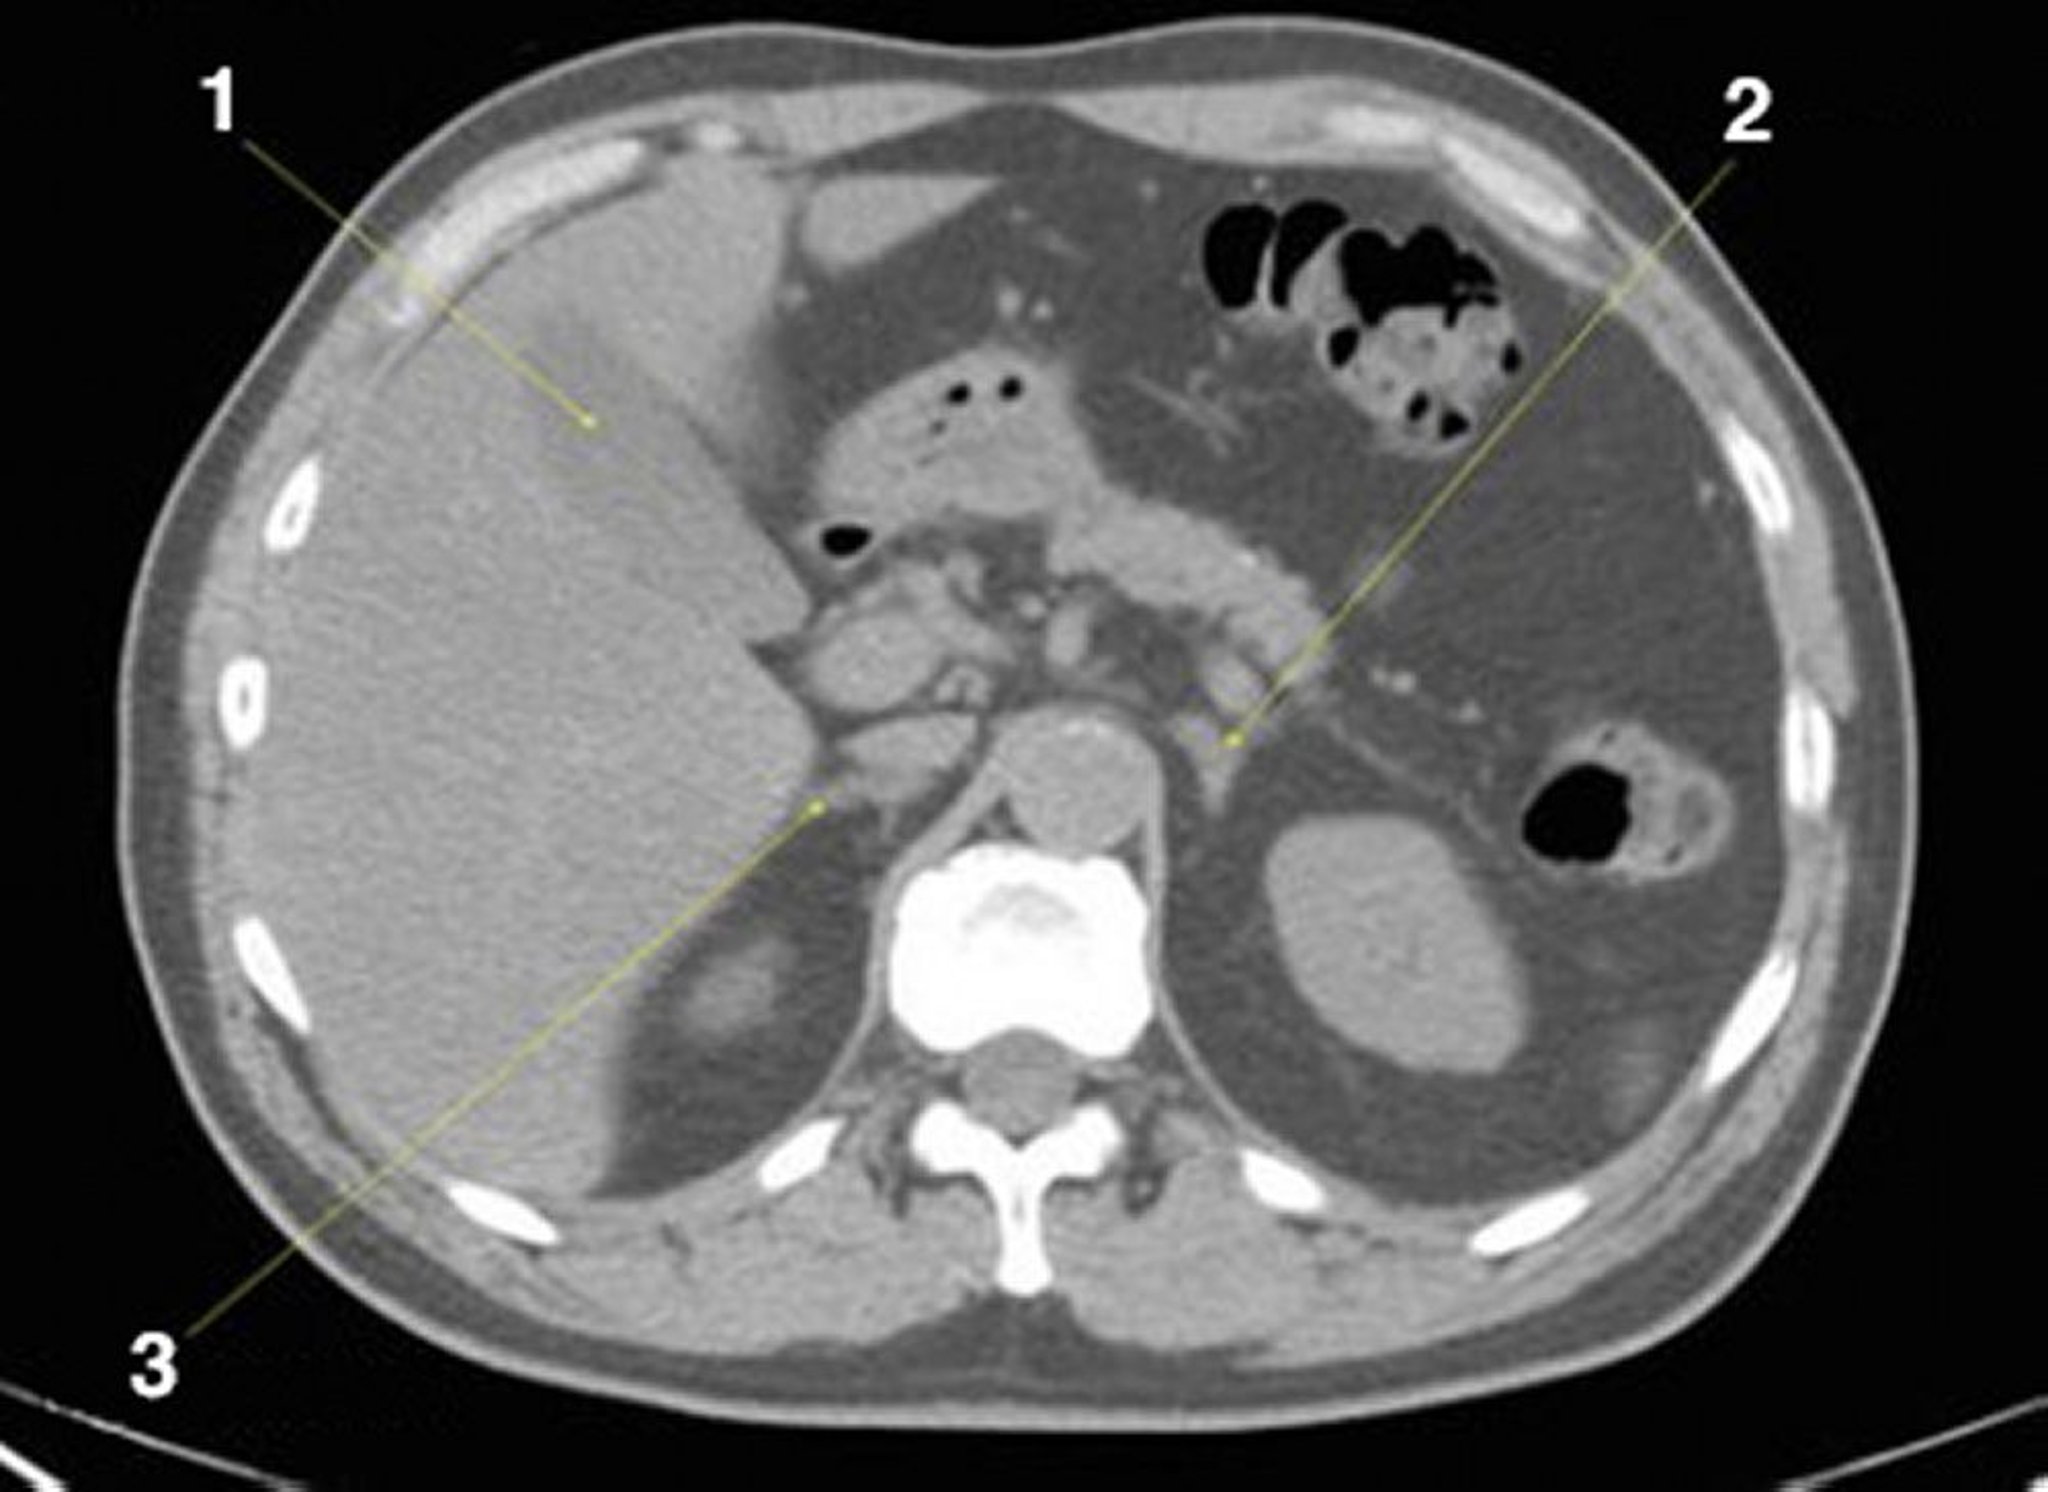

TDM sans contraste de l'abdomen et du bassin montrant une anatomie normale (diapositive 8)

1 = vésicule biliaire; 2 = glande surrénale gauche; 3 = glande surrénale droite.